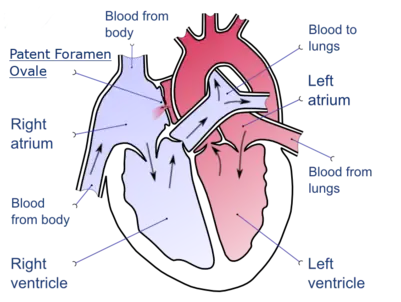

DVT is thought to be able to cause a stroke in the presence of a heart defect. This is called a paradoxical embolism because the clot abnormally travels from the pulmonary circuit to the systemic circuit while inside the heart. The defect of a patent foramen ovale is thought to allow clots to travel through the interatrial septum from the right atrium into the left atrium.[37][38]

A case of phlegmasia cerulea dolens in the left leg A depiction of a patent foramen ovale

A depiction of a patent foramen ovale